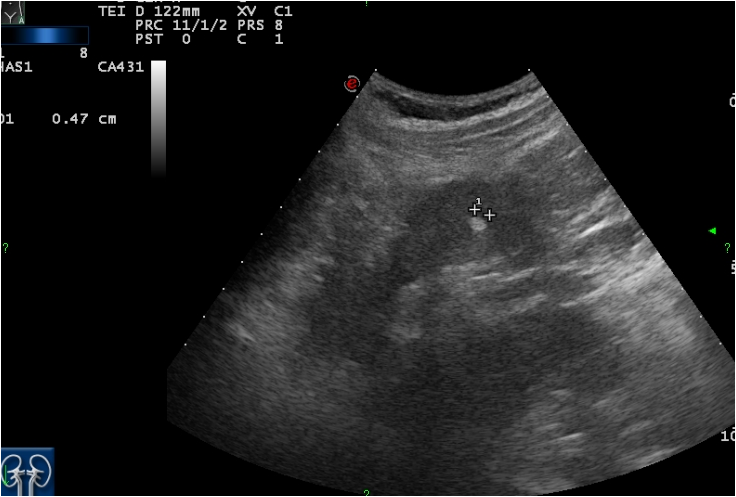

Image

Figure 4. Angiomyolipoma (well circumscribed hyperechoic mass) US image